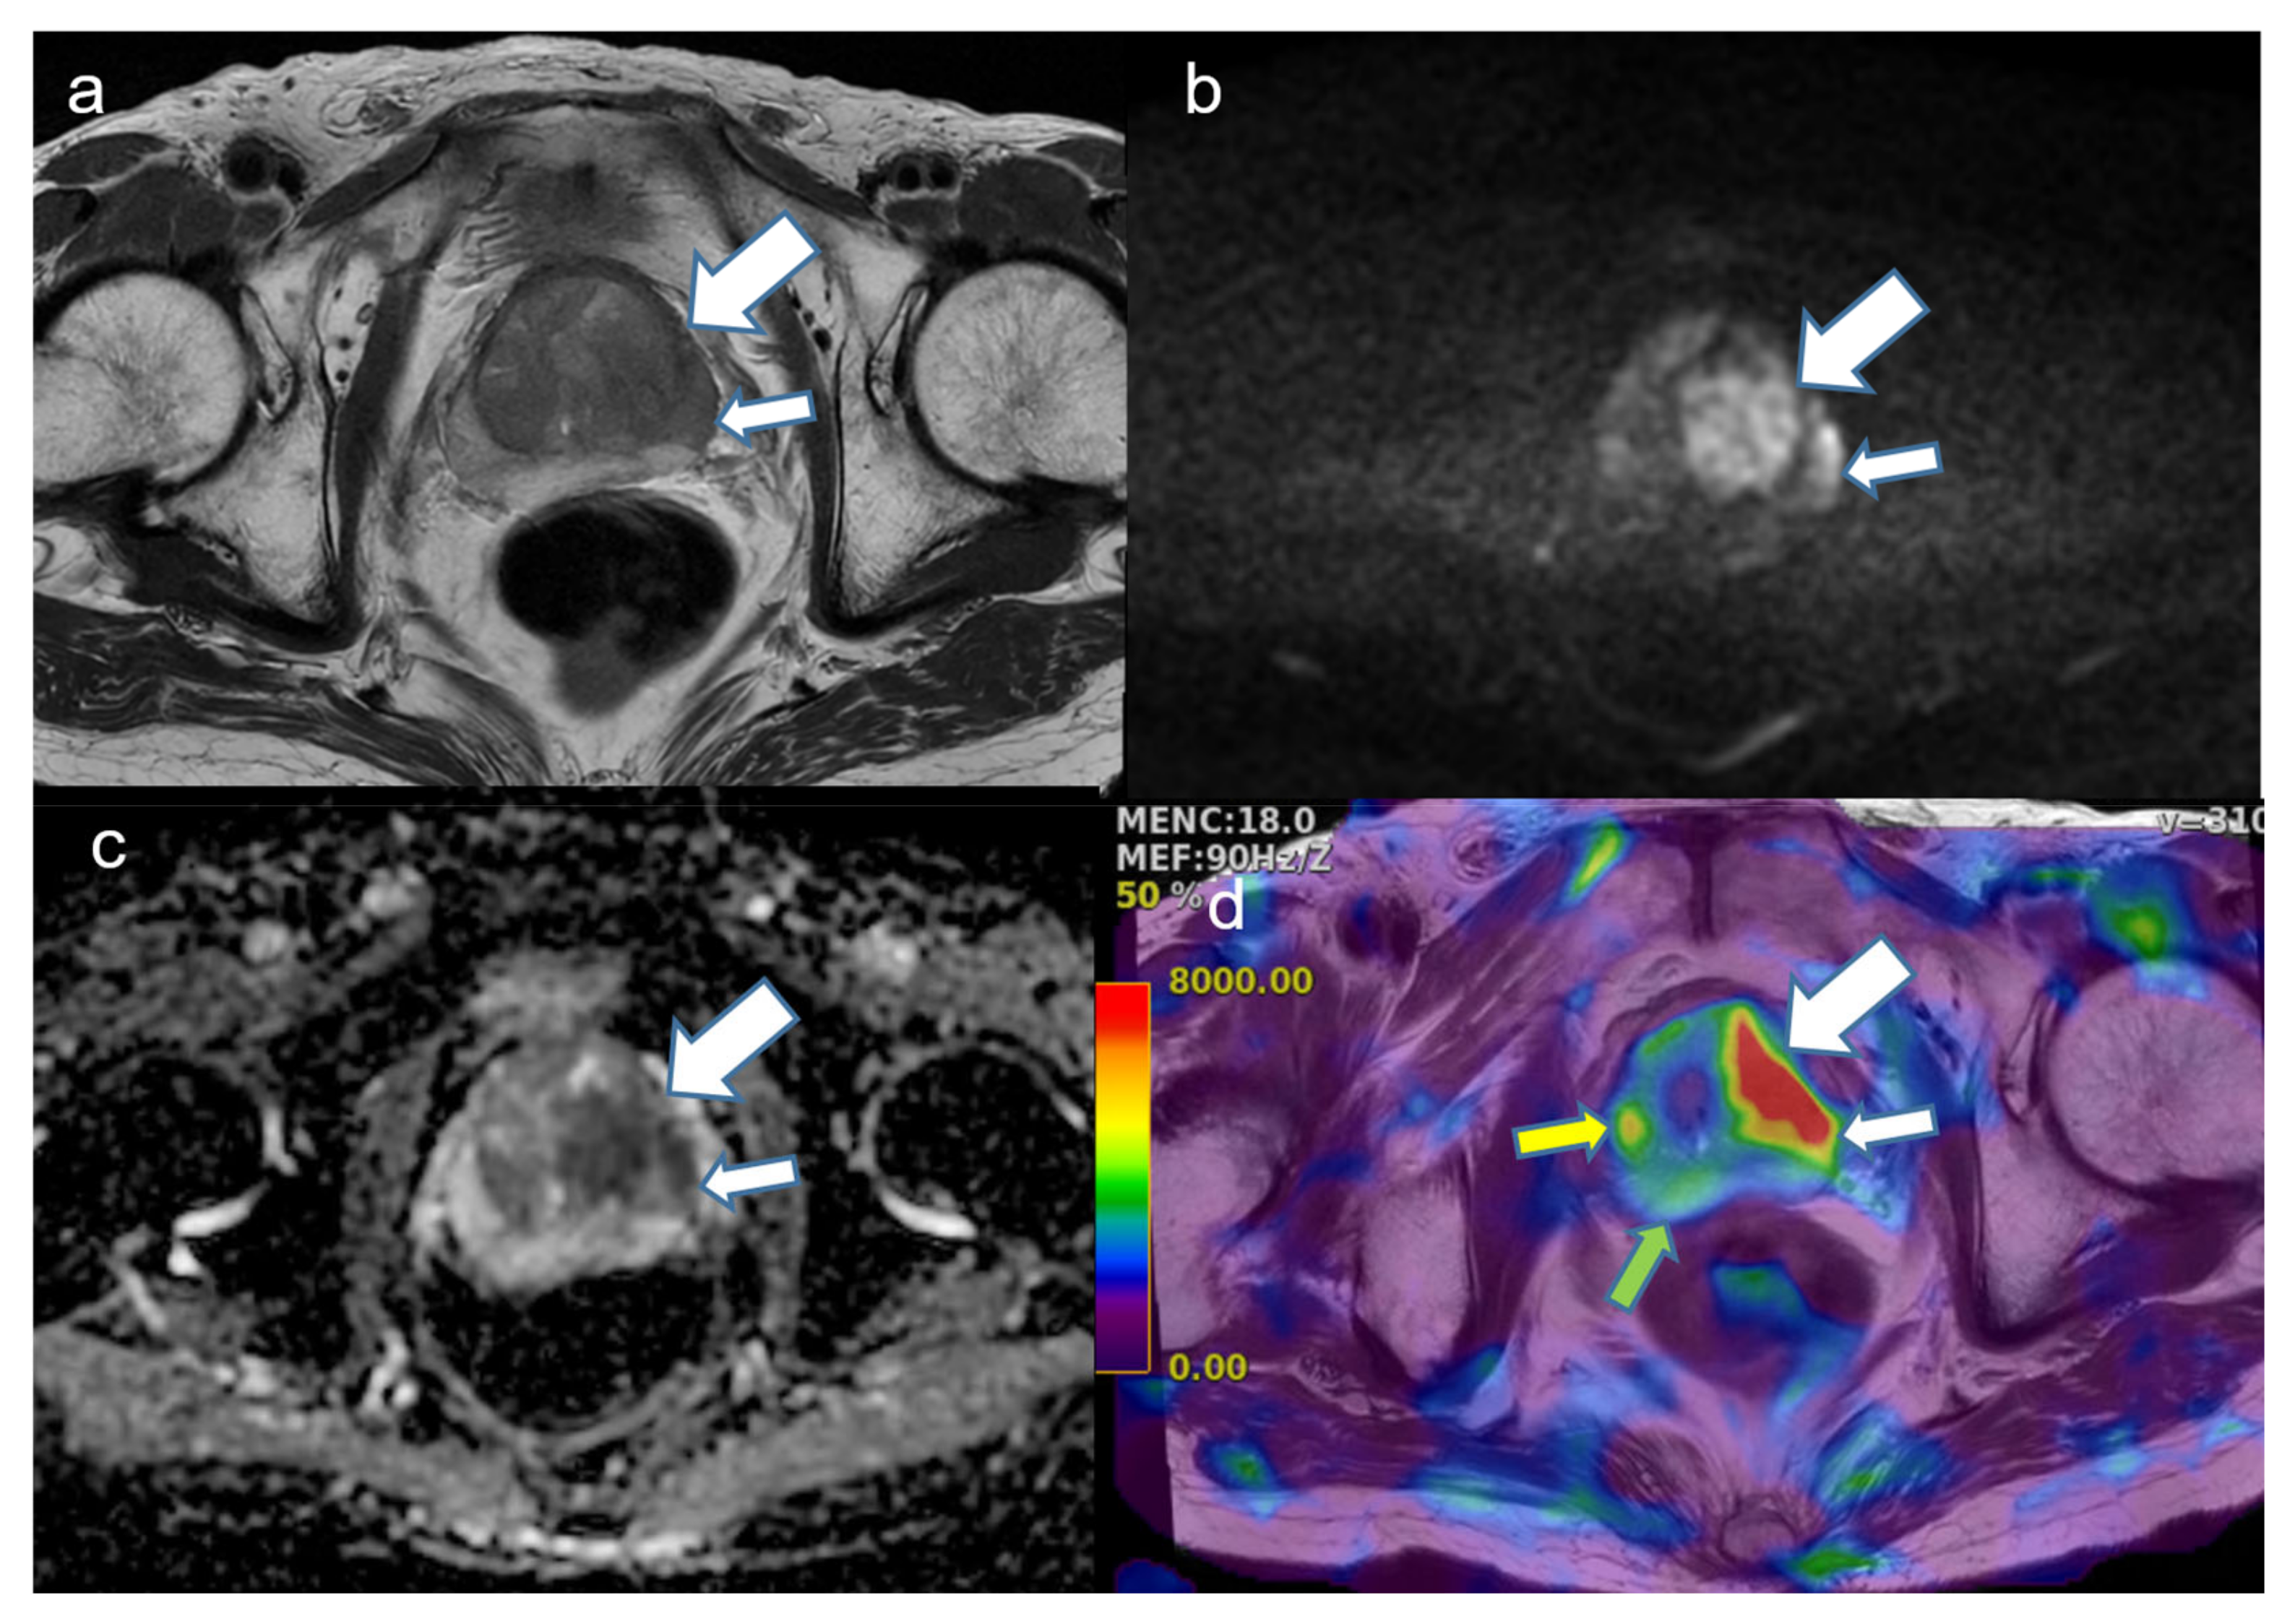

2.4. Image Analysis

4. Discussion